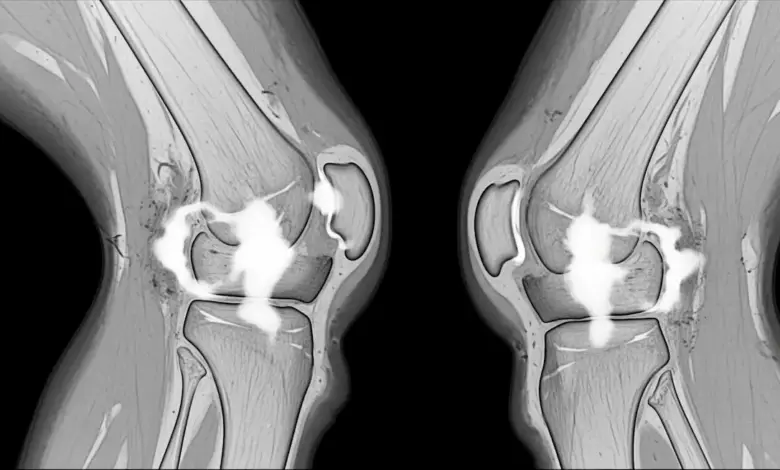

O edema ao redor de um ligamento representa acúmulo de líquido e alteração inflamatória nos tecidos vizinhos, que pode aparecer após torções, impactos, movimentos bruscos ou sobrecarga repetitiva.

Em alguns casos, o ligamento permanece íntegro e o edema reflete apenas uma agressão local. Em outros, o exame pode estar mostrando a repercussão de uma lesão parcial ou completa.

- Qual ligamento está relacionado ao edema?

- Existe lesão parcial ou ruptura?

- O joelho apresenta frouxidão?

- Há lesão meniscal associada?

- Existe contusão óssea, derrame ou dano condral?

Depois disso, a ressonância ajuda a detalhar as estruturas envolvidas. Radiografias também podem ser indicadas, principalmente quando há trauma importante, dor persistente ou suspeita de lesão óssea associada.